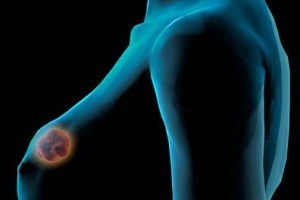

"A Campanha Internacional de Prevenção do Câncer de Mama,...